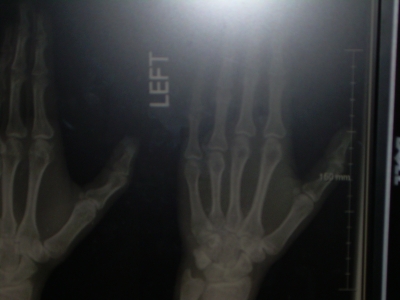

3. The potential image manipulation when dealing with X-rays is AWESOME to any gadget appreciator. You can zoom in, play with contrast... really if it hadn't been my own bones I'd been looking at I would have found it entirely fun.

Ooo! Can you get hold of the xrays next time you visit the doctor? Or snap a picture of them?